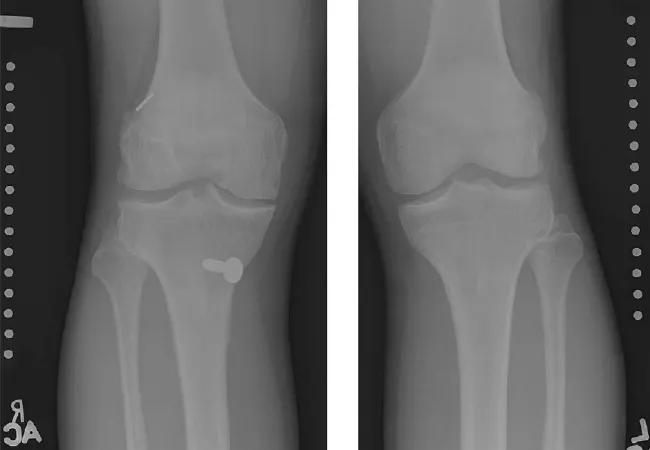

Images from a 13-year-old female patient who had a normal medial meniscus and a medial compartment mJSW 1.97 mm wider on the ACL-reconstructed side compared with the contralateral control side.